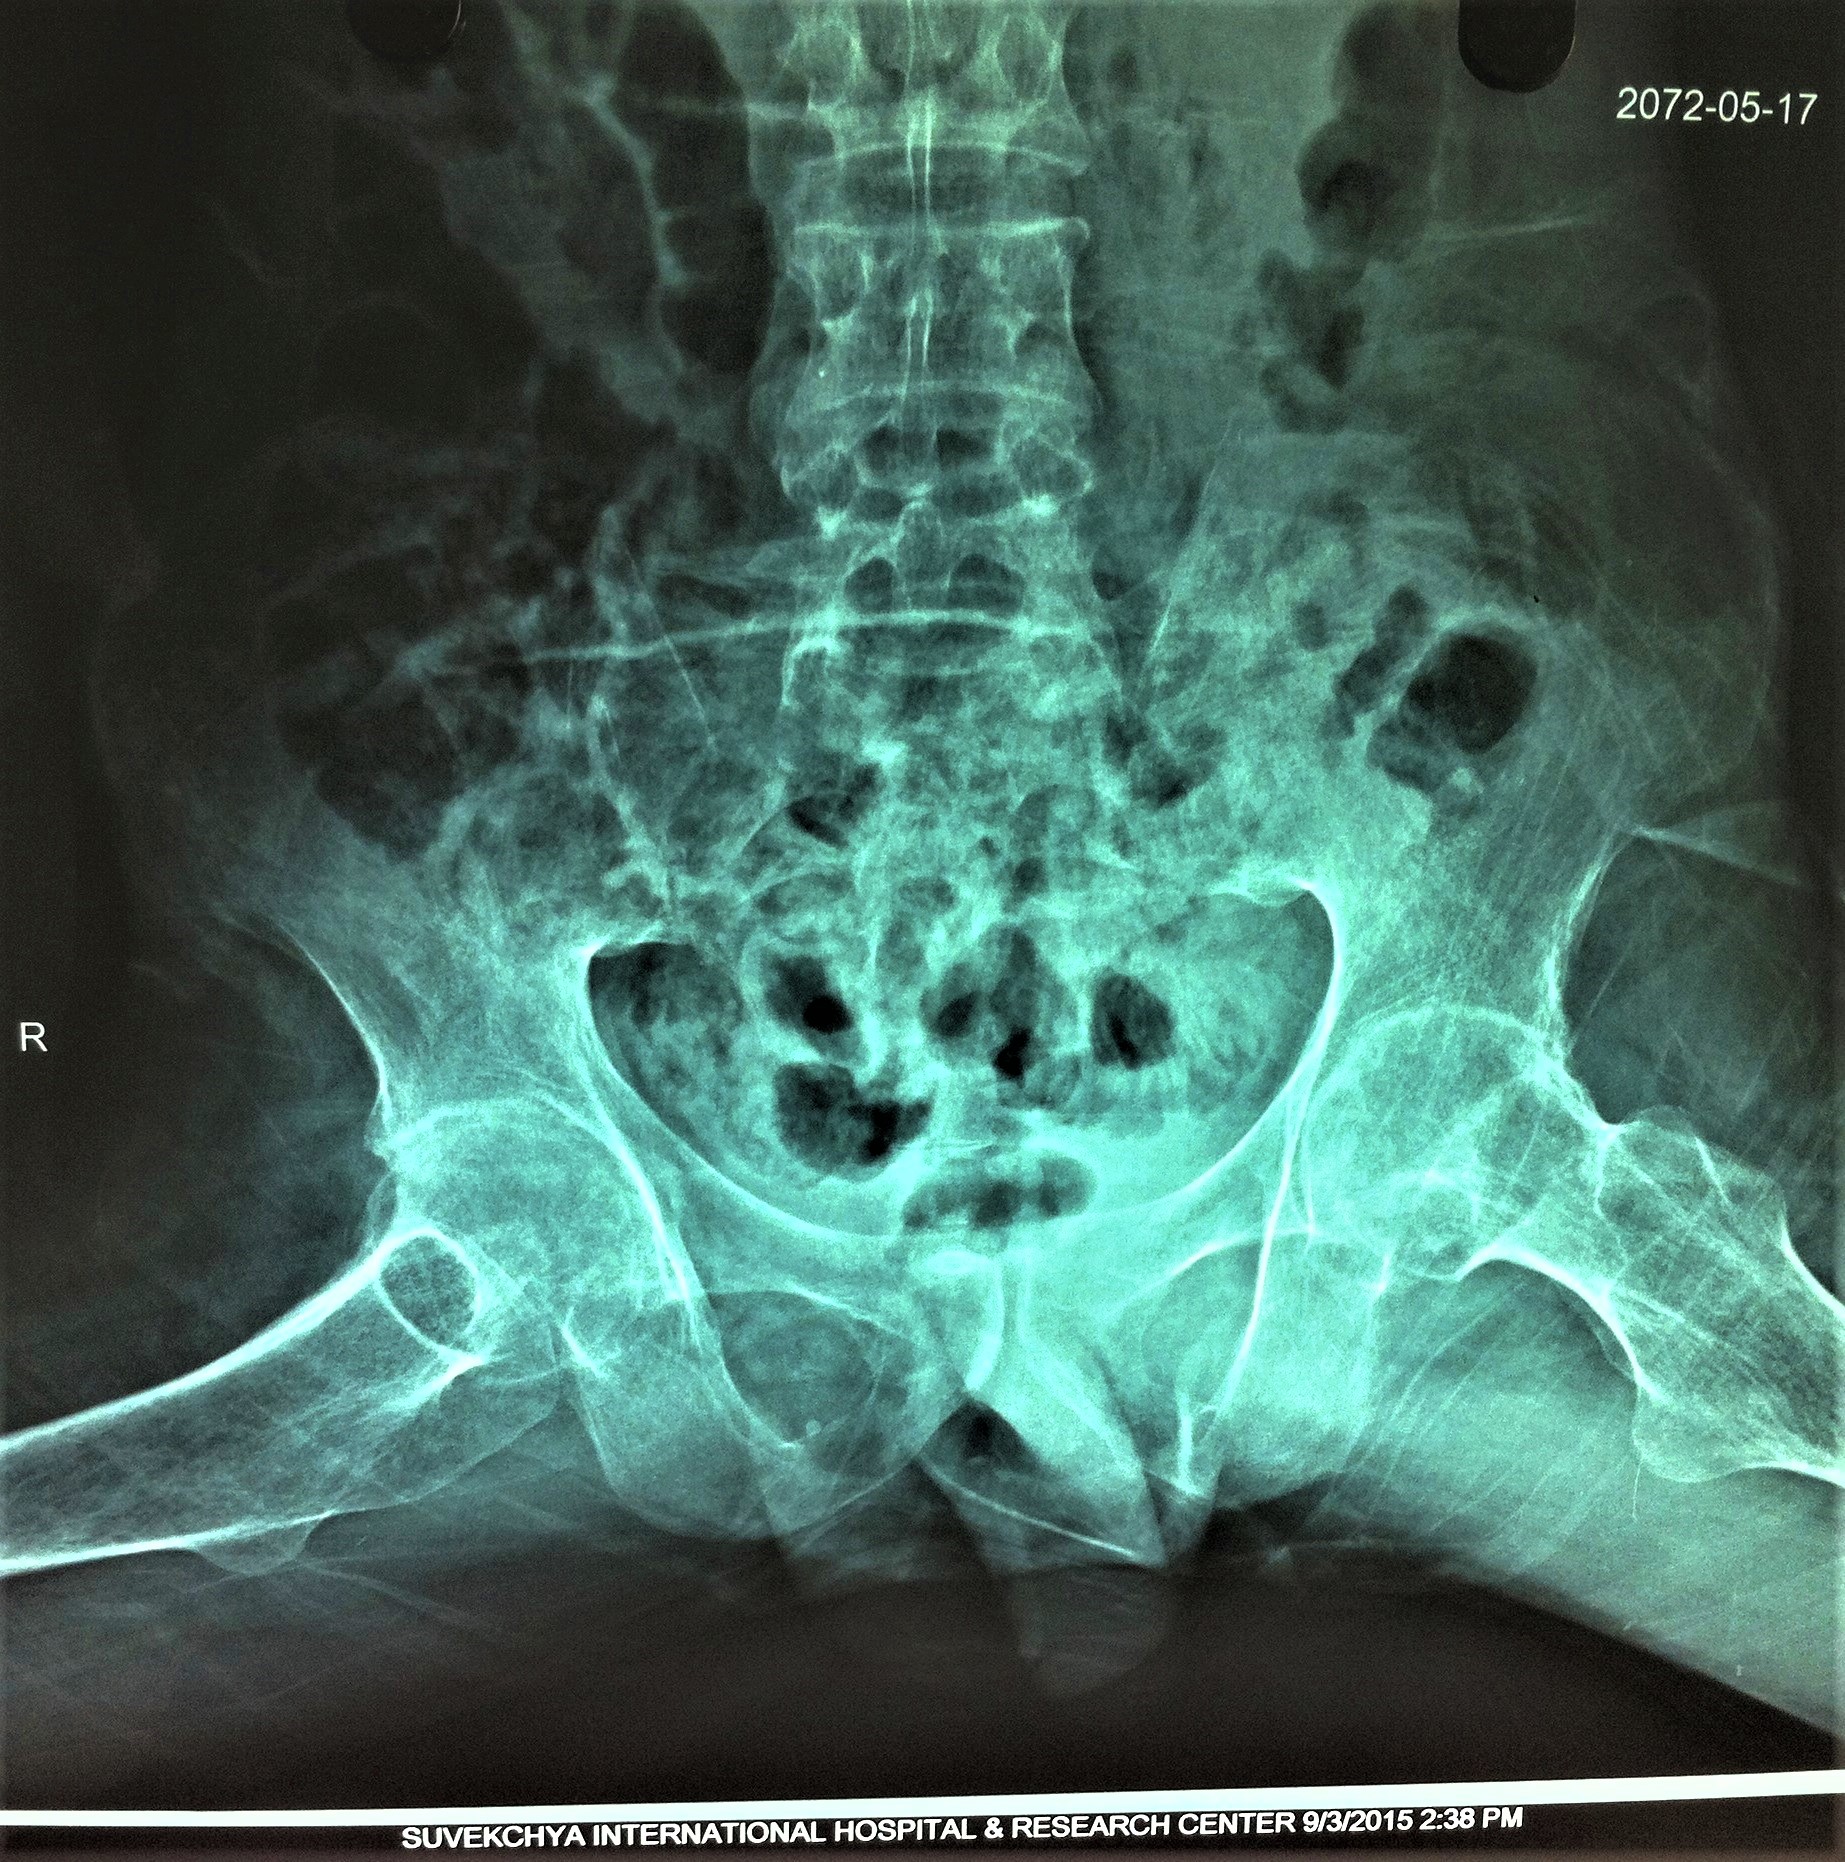

- Initial X Ray